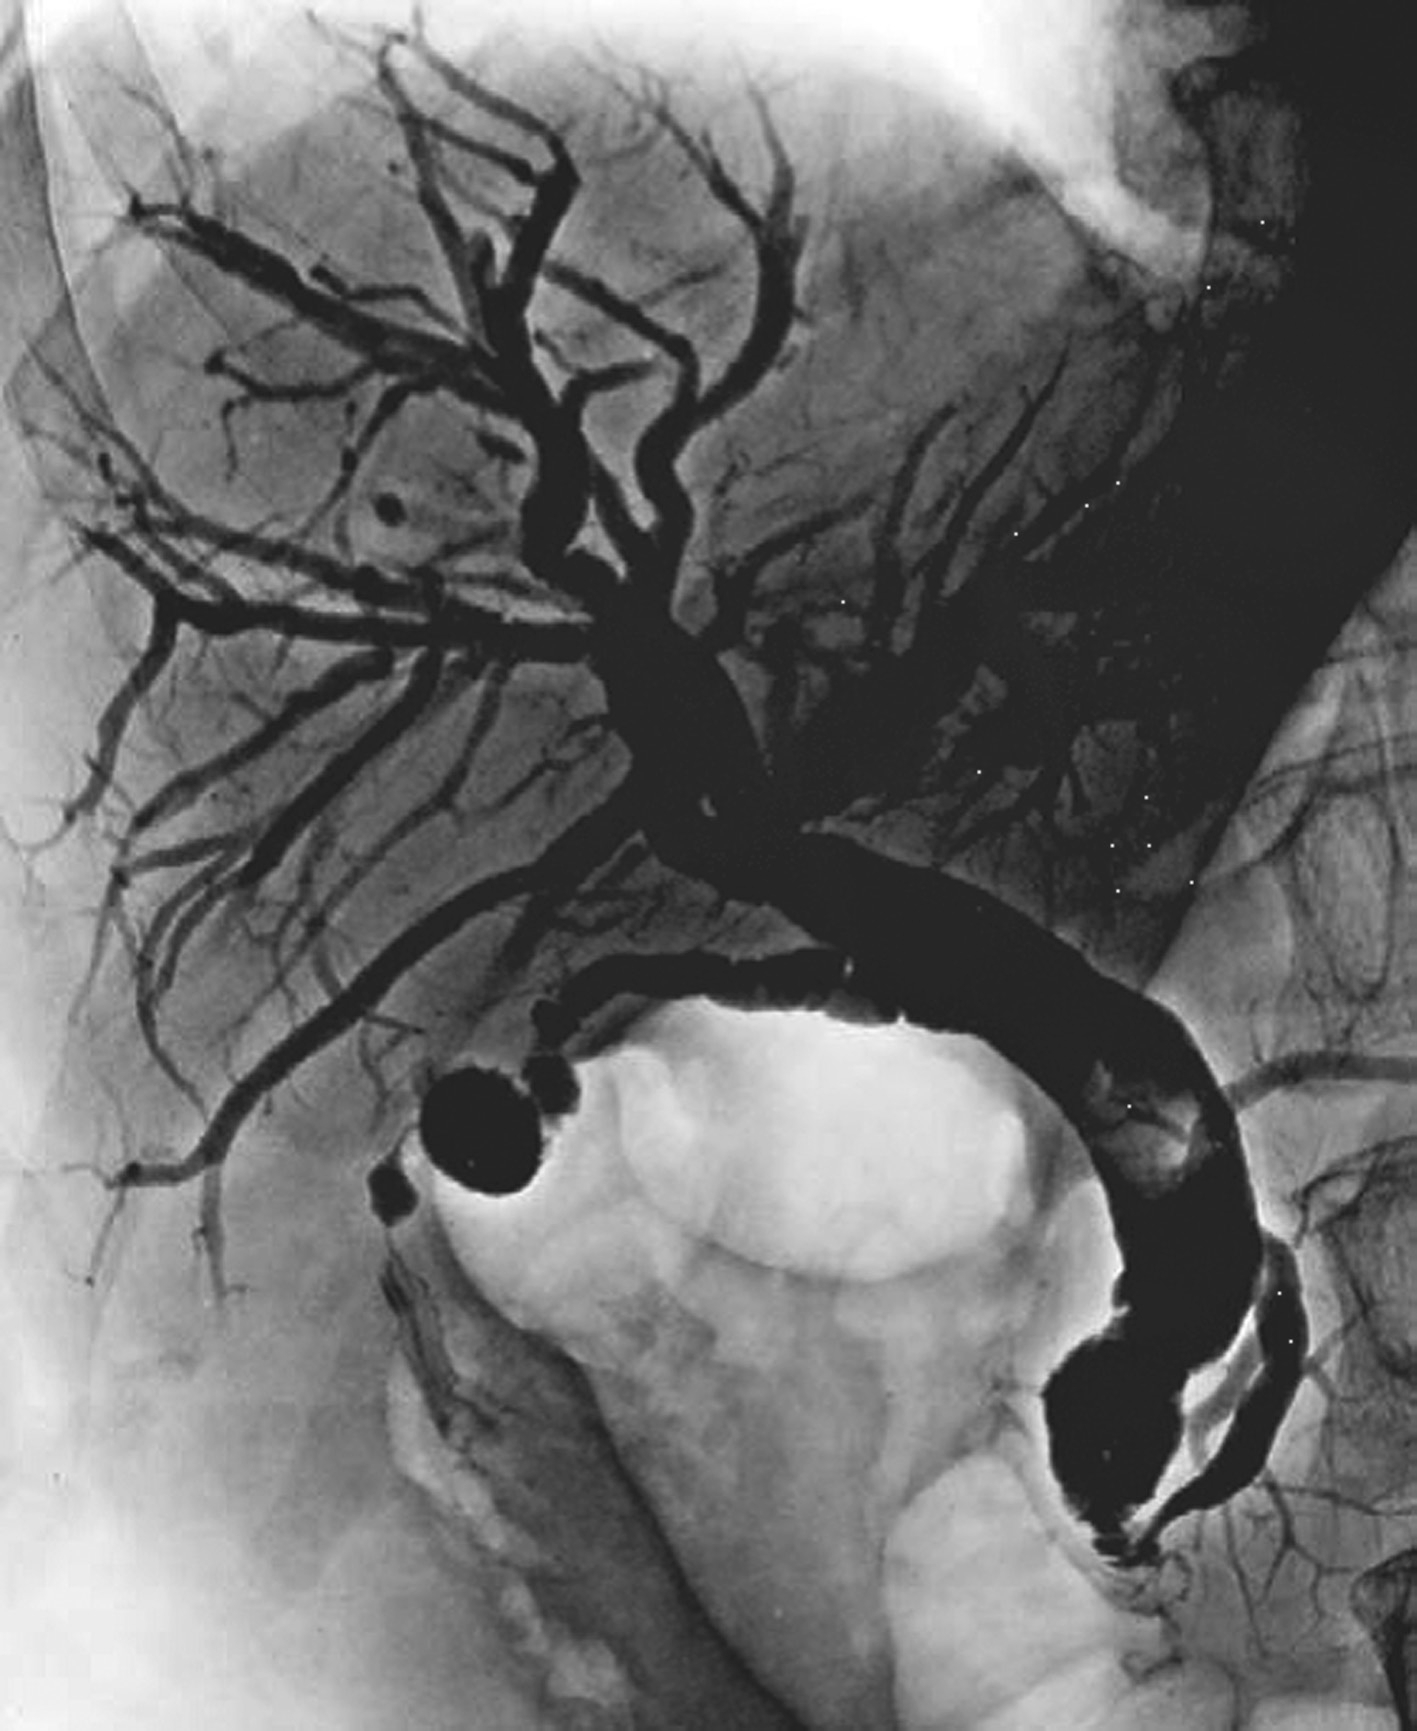

采用Seldinger技术穿刺股动脉成功后,插管入肝总动脉,行动脉造影,常规采用非离子碘对比剂,以6~8mL/s,总量20~30mL的速率注入,并连续摄片12秒以上,以观察肝总动脉及其分支,动脉供养器官的实质期和静脉回流的情况(图5-21-49)。如需要进一步观察肝脏的情况,可以超选择插管进入肝固有动脉或者肝左、右动脉。如经股动脉插管不成功,亦可选择经肱动脉和桡动脉等上入路。显示肝动脉和肝实质及回流静脉的情况,可有:①常规X线摄片检查,已被数字减影血管造影(digital subtraction angiography,DSA)取代;② DSA,是应用计算机辅助成像。动脉插管成功后,注入造影剂之前,首先进行第一次成像,并用计算机将图像转换成数字信号储存起来。注入造影剂后,再次成像并转换成数字信号。两次数字相减,消除相同的信号,得知一个只有造影剂的血管图像。这种图像可以更清晰和直观显示血管结构。显示血管的情况,除插管进入动脉后注入对比剂外,亦可经静脉注入对比剂后,根据对比剂的循环时间观察其显示的相应的血管。如CT动脉造影(CT angiography,CTA),将CT增强技术与薄层、大范围、快速扫描技术相结合,通过合理的后处理,清晰显示全身各部位血管细节,具有无创和操作简便的特点,对于血管变异、血管疾病以及显示病变和血管关系有重要价值。

图5-21-49 经股动脉穿刺行肝总动脉造影

A.可观察肝总动脉及其分支,动脉期可见肝右下富血供性占位病变(白色箭头);B.静脉期可见脾静脉和门脉干及其分支显示

间接门脉造影即插管入脾动脉和/或肠系膜上动脉后,注入4~5mL/s,总量25~30mL造影剂,延长观察时间,不仅观察动脉期和实质期,还要观察对比剂回流后显示的门静脉期(图5-21-51)。间接门脉造影的操作相对简单,但通过对比剂的回流显示门脉,可受门脉循环时间和对比剂量的影响,且无法用来测量门脉压力。

图5-21-51 经肠系膜上动脉间接门脉造影

A.插管入肠系膜上动脉注入造影剂;B.经肠系膜上静脉回流后,可显示肠系膜上静脉、门脉干和门脉的分支